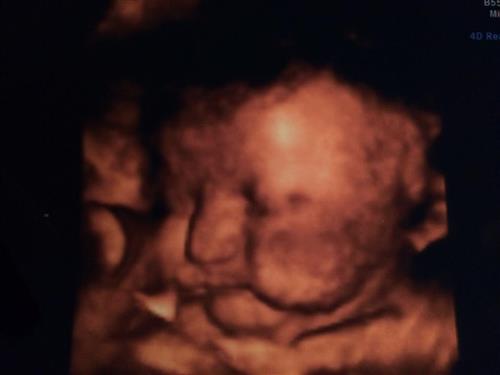

33w:

Few hours old:

Posted by ElizaRags35

33w: IMAGE

Few hours old: IMAGE

Aww she's beautiful!!!!

Wow you could definitely see her in that 4D pic!!